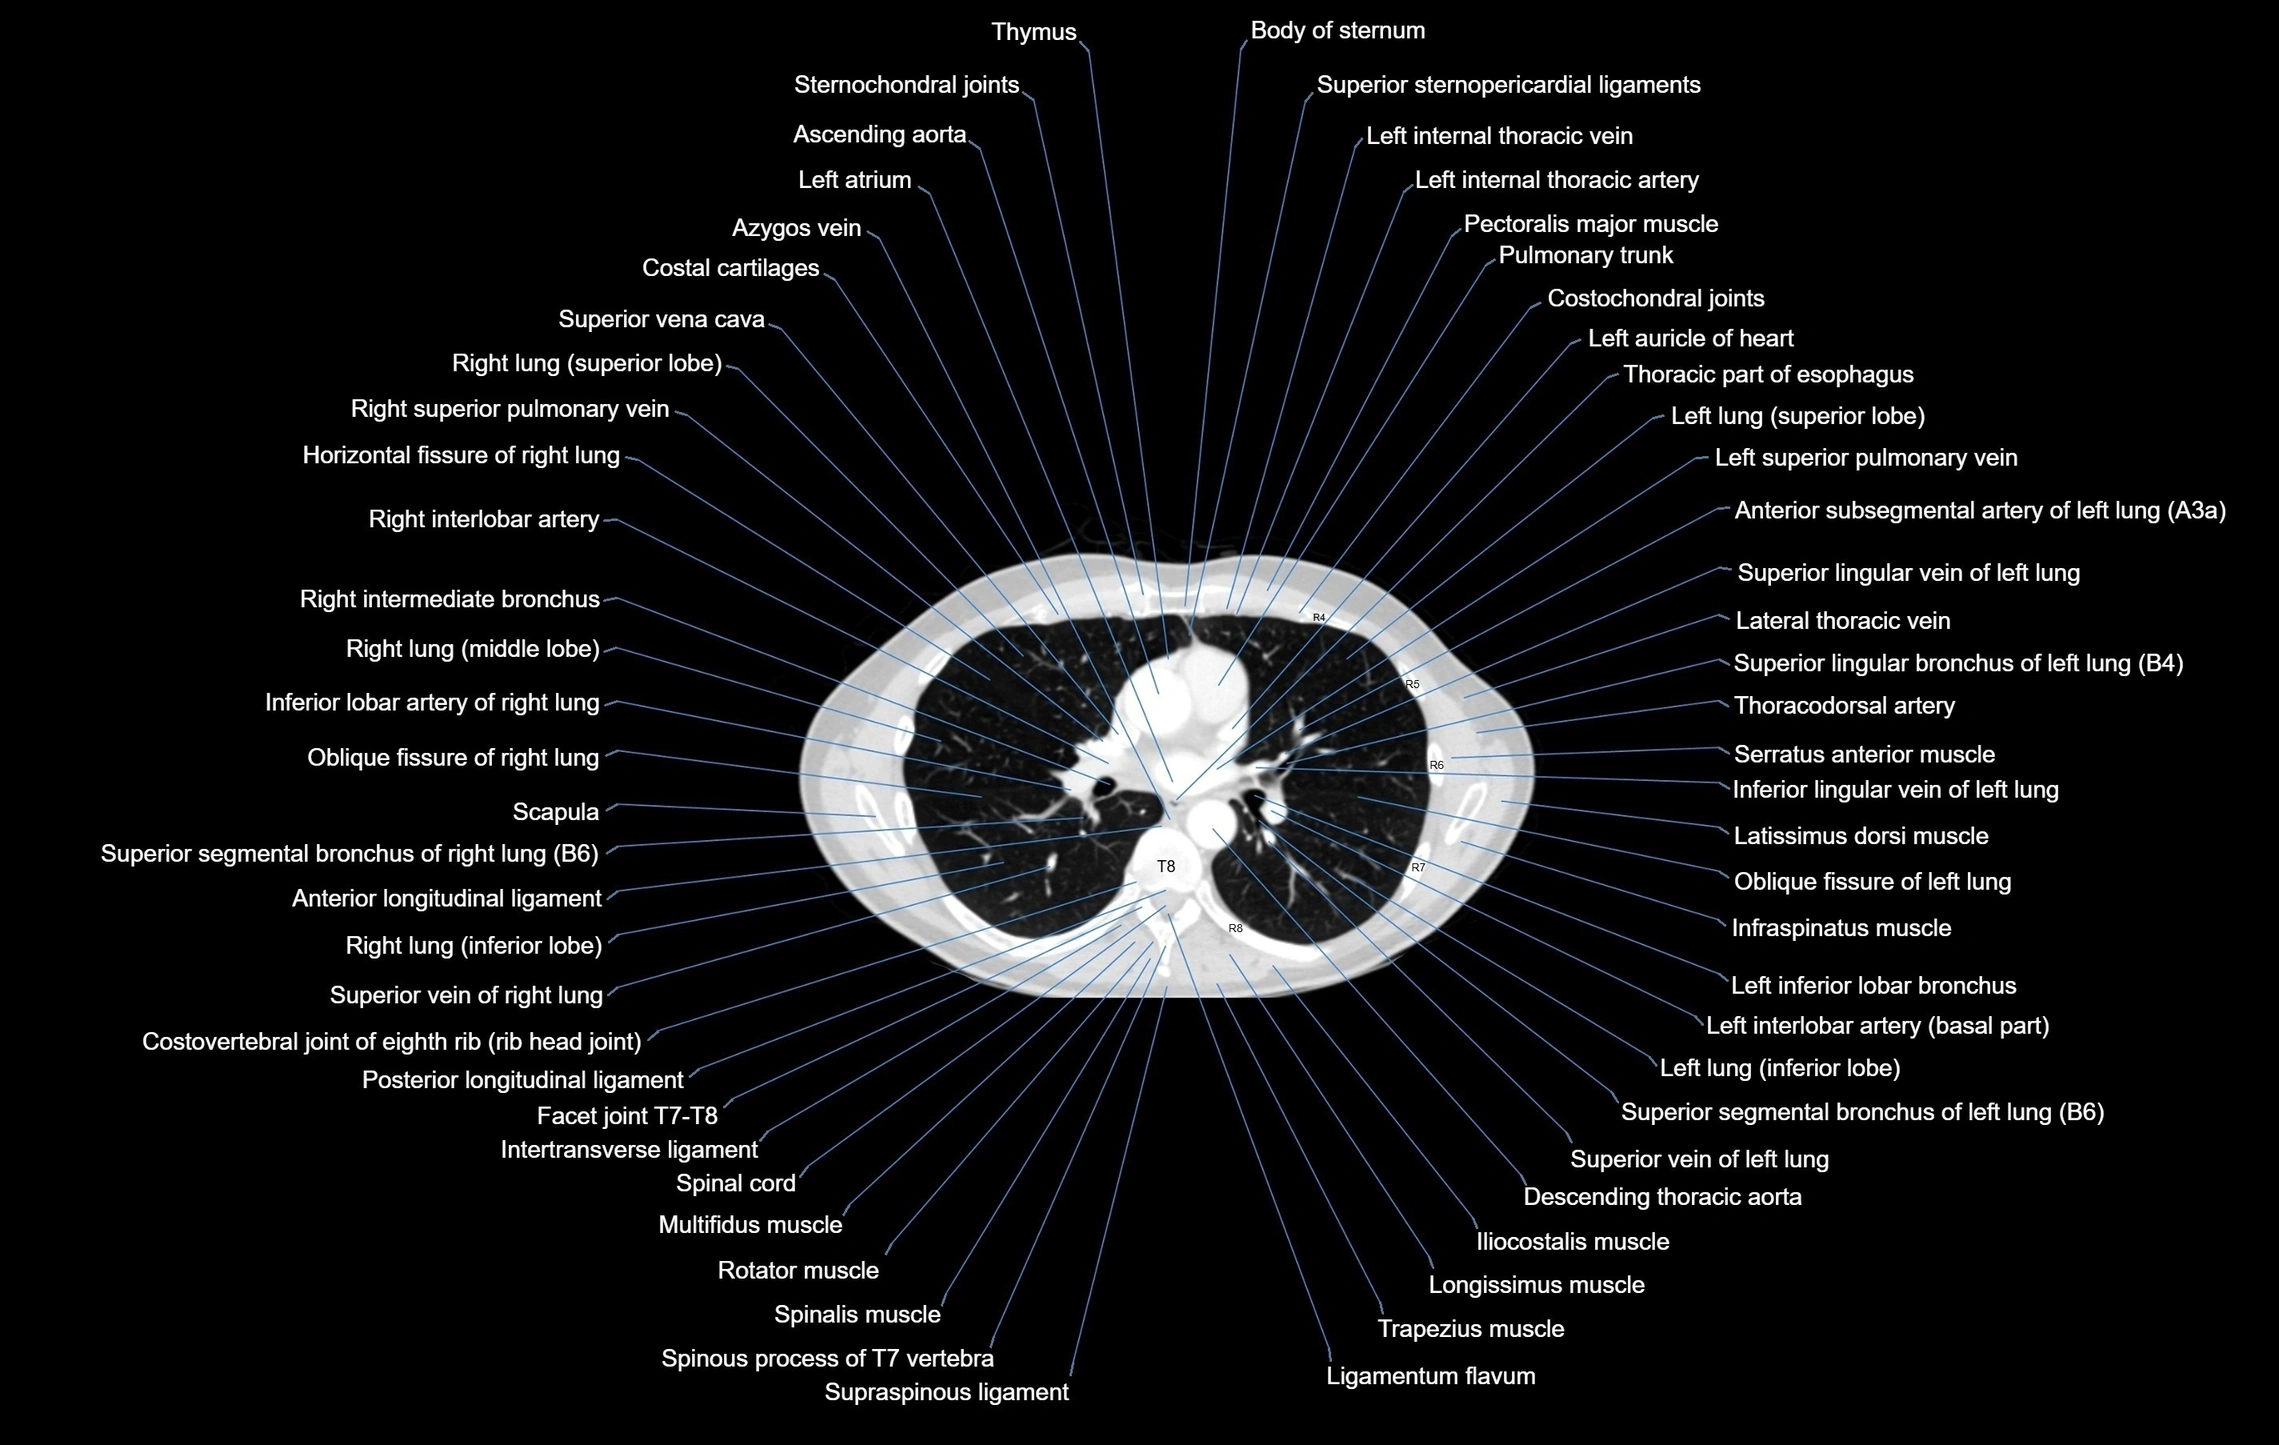

CT images